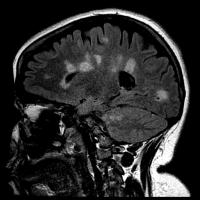

Multiple Sclerosis Scarring of Brain

image: This is an MRI of a person with multiple sclerosis. White areas show permanent scarring caused by the disease. view more

Magnetic resonance imaging (MRI) of their brains was used to count the number of new lesions in their myelin, and researchers found no difference after six months and after one year between the treatment group and the sham group.